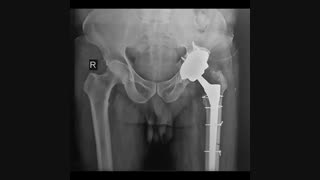

چه موقع یک بیمار مبتلا به شکستگی استابولوم نیاز به جراحی تعویض مفصل ران و لگن پیدا میکند و جراحی تعویض مفصل در چه زمانی و به چه نحو میتواند به درمان خود شکستگی و عوارض شکستگی استابولوم کمک کند.